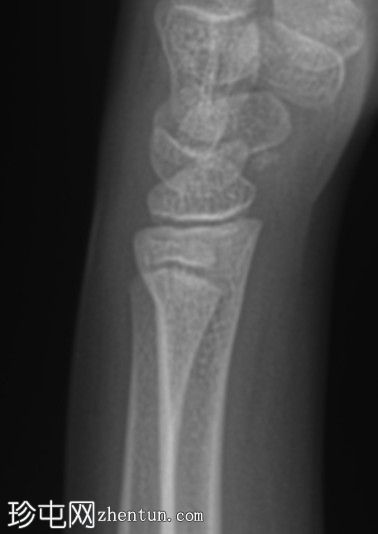

侧位片

桡骨远端干骺端皮质骨隆起,符合骨性骨折(Cuckle fracture)的特征。

骨性骨折(Cuckle fracture)是指长骨干的不完全性骨折,其特征是皮质骨隆起;常见于儿童,常累及桡骨远端干骺端。